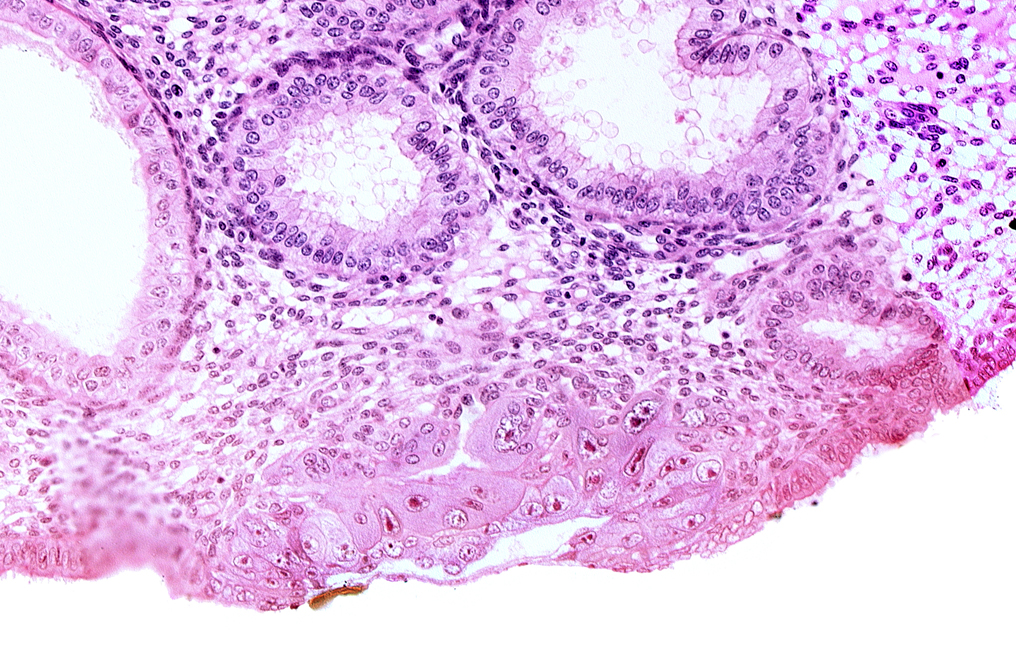

Carnegie Embryo #8020 | Location: 06-01-01

Keywords: blastocystic cavity (blastocoele), cytotrophoblast, embryonic disc, endometrial sinusoid, extra-embryonic mesoblast, membranous trophoblast at abembryonic pole, solid syncytiotrophoblast

Source: The Virtual Human Embryo.